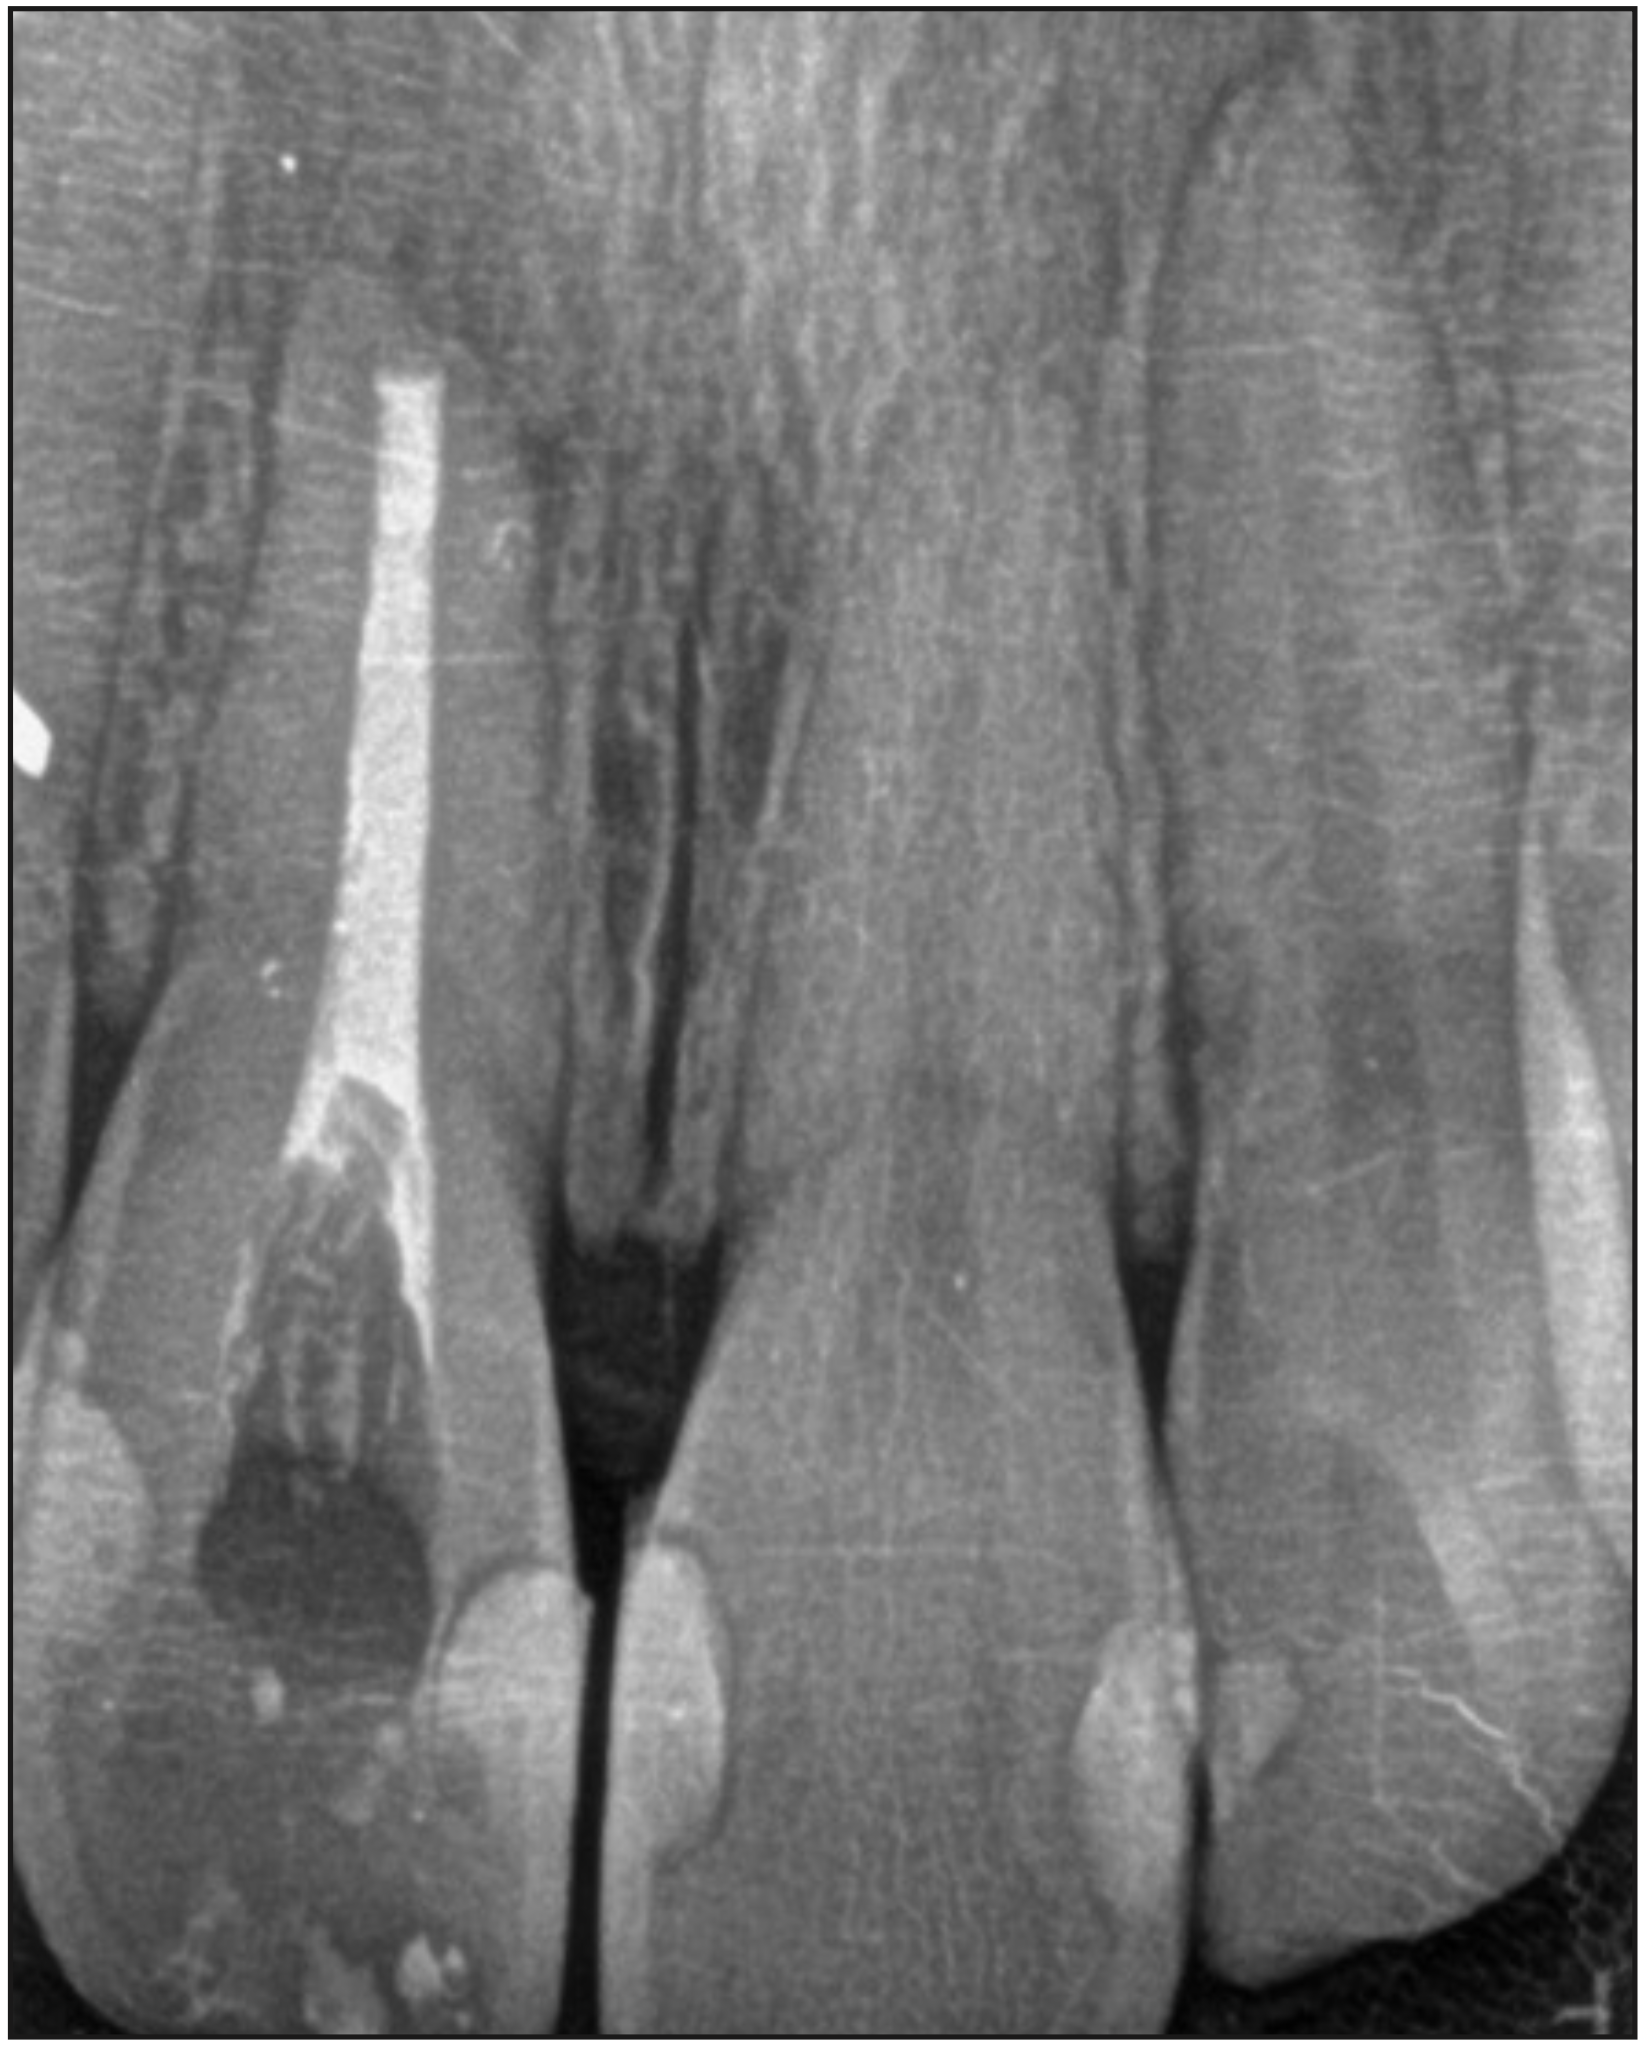

A continuación, se rellenó el lecho quirúrgico con matrices de fibrina rica en plaquetas obtenidas del propio paciente y se utilizó otra matriz del mismo material para proteger el área de la osteotomía antes de la reposición del colgajo y síntesis efectuada a través de puntos simples interrumpidos con sutura reabsorbible (Vicryl 5/0 Ethicon® Ohio, Estados Unidos). Los signos vitales de la paciente se mantuvieron estables durante todo el procedimiento y la muestra del tejido extirpado fue enviada a biopsia. Al finalizar, se tomó radiografía de control del procedimiento realizado.

Figura 4. Radiografía de control inmediato post microcirugía y obturación endodóntica simultánea. Se observa exceso de gutapercha en zona cervical que fue corregido en sesión de control posterior.